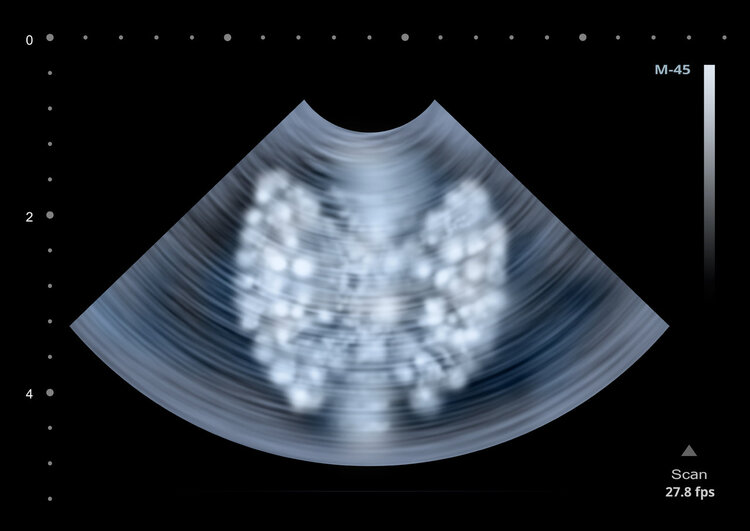

甲状腺瘤回声高与低的区别

甲状腺瘤超声检查有回声高与低的区别,回声高者超声下比周围组织回声高内部较均匀光线反射强含较多纤维组织良性可能相对高边界清形态规则血流信号不丰富,回声低者超声下比周围组织回声低内部结构复杂有恶变潜在风险边界可清或不清形态可不规则血流信号可能丰富不同人群中临床意义有相似判断逻辑儿童需密切观察女性要考虑生理周期特殊病史人群需严格多方面评估。